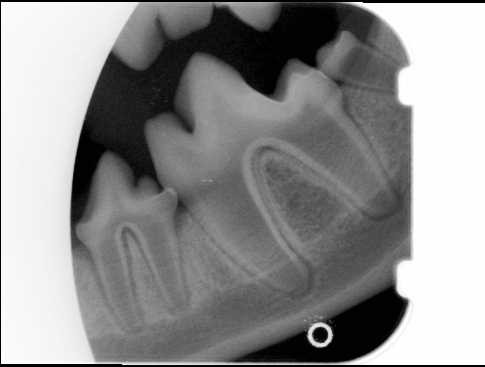

cat path 1-4